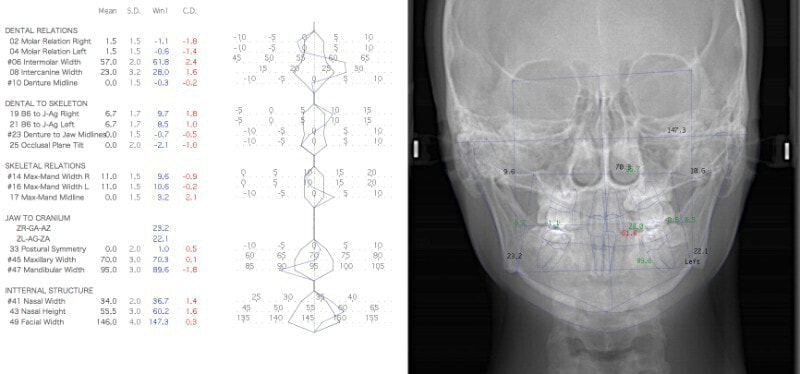

検査時のセファロ分析側貌

上顎劣成長の値が出ています。顔面、下顎骨骨体自体は標準偏差1S.D.内に収まっています。

顔面と顎骨の幅径はある程度確保されているので、非抜歯が可能であると診断しました。

治療後のセファロ分析です。

反対咬合の治療は、FX(フェイシャルアキシス)が開きやすいのですが、治療後も良好な値を保つことができました。FXがあまり開きすぎると、咬合力が落ちてしまいます。

下顎の右側への偏位は解消されました。

大臼歯は整直されております。